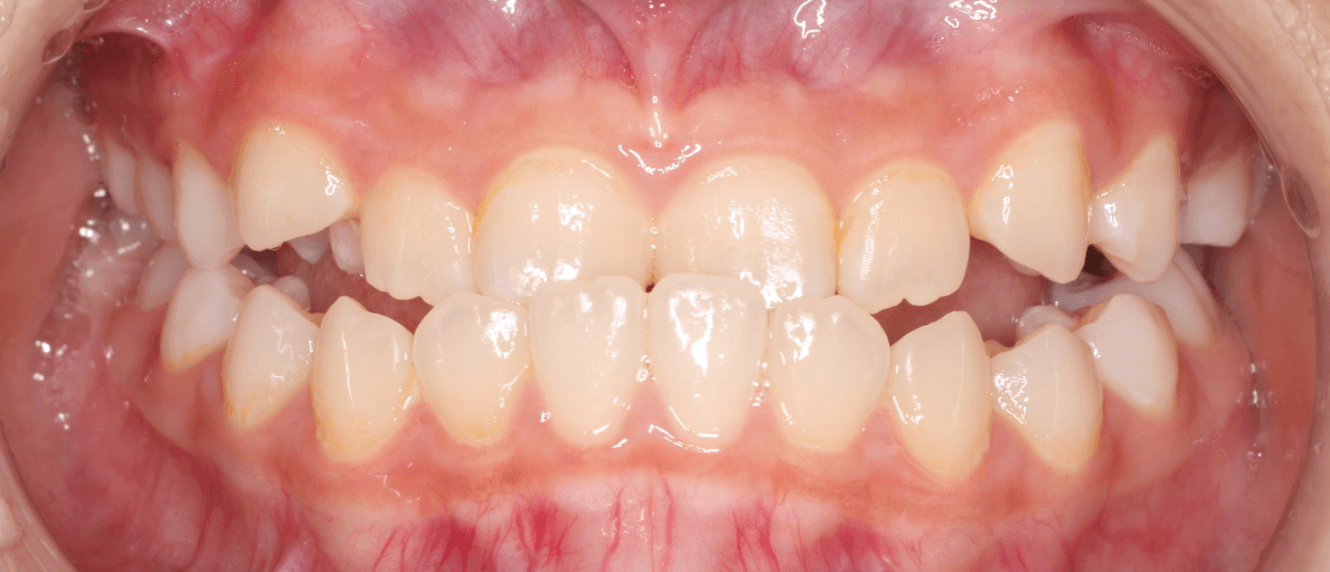

混合歯列期後期の受け口

10歳前後の乳歯と永久歯が混ざっている混合歯列期後期は、治療可能なケースが少なくなります。これは永久歯列完成に向けての移行期であり、下あごの思春期性成長が始まる時期が迫っているからです。矯正装置を使用して反対咬合を改善しようとしても変化がないか、すぐ後戻りしてしまいやすい時期です。

下あごの成長は身長や骨格の成長のピークの近似しています。したがって、中程度〜重度の反対咬合は、男子は18歳、女子は15歳までは治療待機します。

男子では治療は見送ることが多いのですが、成長期が短い女子の場合は「切端咬合位」がとれるような軽度な反対咬合であれば混合歯列期で10代前半でも、保護者の方に成長による効果軽減のリスクをご理解のもと矯正治療を開始することもあります。

ただし、安易な治療介入は、かえって良い結果が得られない可能性もあります。治療の必要性が高いケースでも、あごの成長のタイミングを見極めながら、慎重に方針を決定していくことが肝心です。